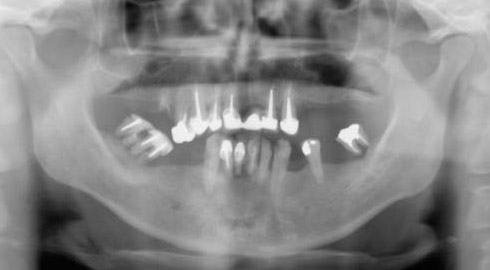

Exemple d’une réhabilitation complète implantaire

Situation clinique initiale

Situation clinique terminée